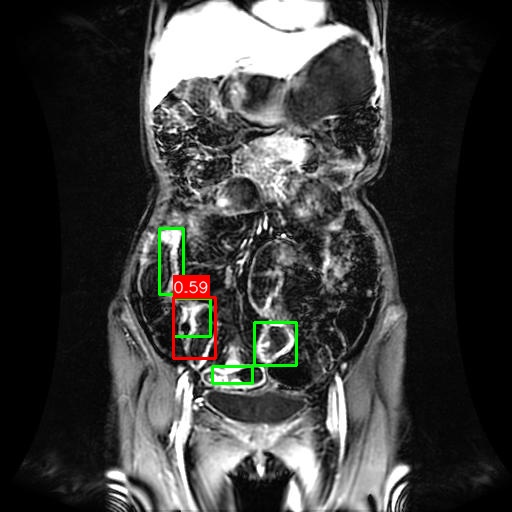

(a) Mask R-CNN [He2017MaskRCNN]

(b) DiffusionDet [Chen2023DiffusionDet_ICCV]

(c) DeFloMat (Ours)

Figure 3: Qualitative Comparison on Crohn’s Disease MRE Test Set. The figure compares detection results from (a) Mask R-CNN, (b) DiffusionDet (S=3S=3), and (c) DeFloMat (Ours, S=3S=3) on challenging MRE slices. Green boxes indicate True Positives (TP, IoU 0.1\geq 0.1), Red boxes indicate False Positives (FP), and Purple boxes indicate False Negatives (FN). DeFloMat consistently demonstrates superior localization quality and sensitivity: it successfully detects subtle inflammation regions (TP) that are often missed (FN, Purple boxes) by the Mask R-CNN baseline (Row 2, 4). Furthermore, DeFloMat provides tighter bounding box localization compared to DiffusionDet, confirming the benefit of learning the direct, deterministic flow field. The results show DeFloMat’s robustness in capturing varying sizes and numbers of inflammatory lesions.

Qualitative Assessment.

Figure 3 provides visual evidence of the models’ performance on challenging MRE slices, where inflammatory lesions can be subtle or obscured. The qualitative results underscore DeFloMat’s enhanced localization fidelity. In challenging cases (e.g., Row 2 and 4), Mask R-CNN and DiffusionDet frequently produce False Negatives (FN, Purple boxes), failing to detect clear inflammation sites. In contrast, DeFloMat reliably converts these FNs into True Positives (TP, Green boxes) by providing tighter and more accurate bounding box predictions. This suggests that the deterministic velocity field learned via Flow Matching is highly effective at precisely directing the proposal centers towards the true lesion locations, a characteristic that is vital for accurate clinical reporting. DeFloMat’s ability to achieve such precise localization with only S=3S=3 steps highlights its clinical utility for rapid diagnostic auxiliary systems.